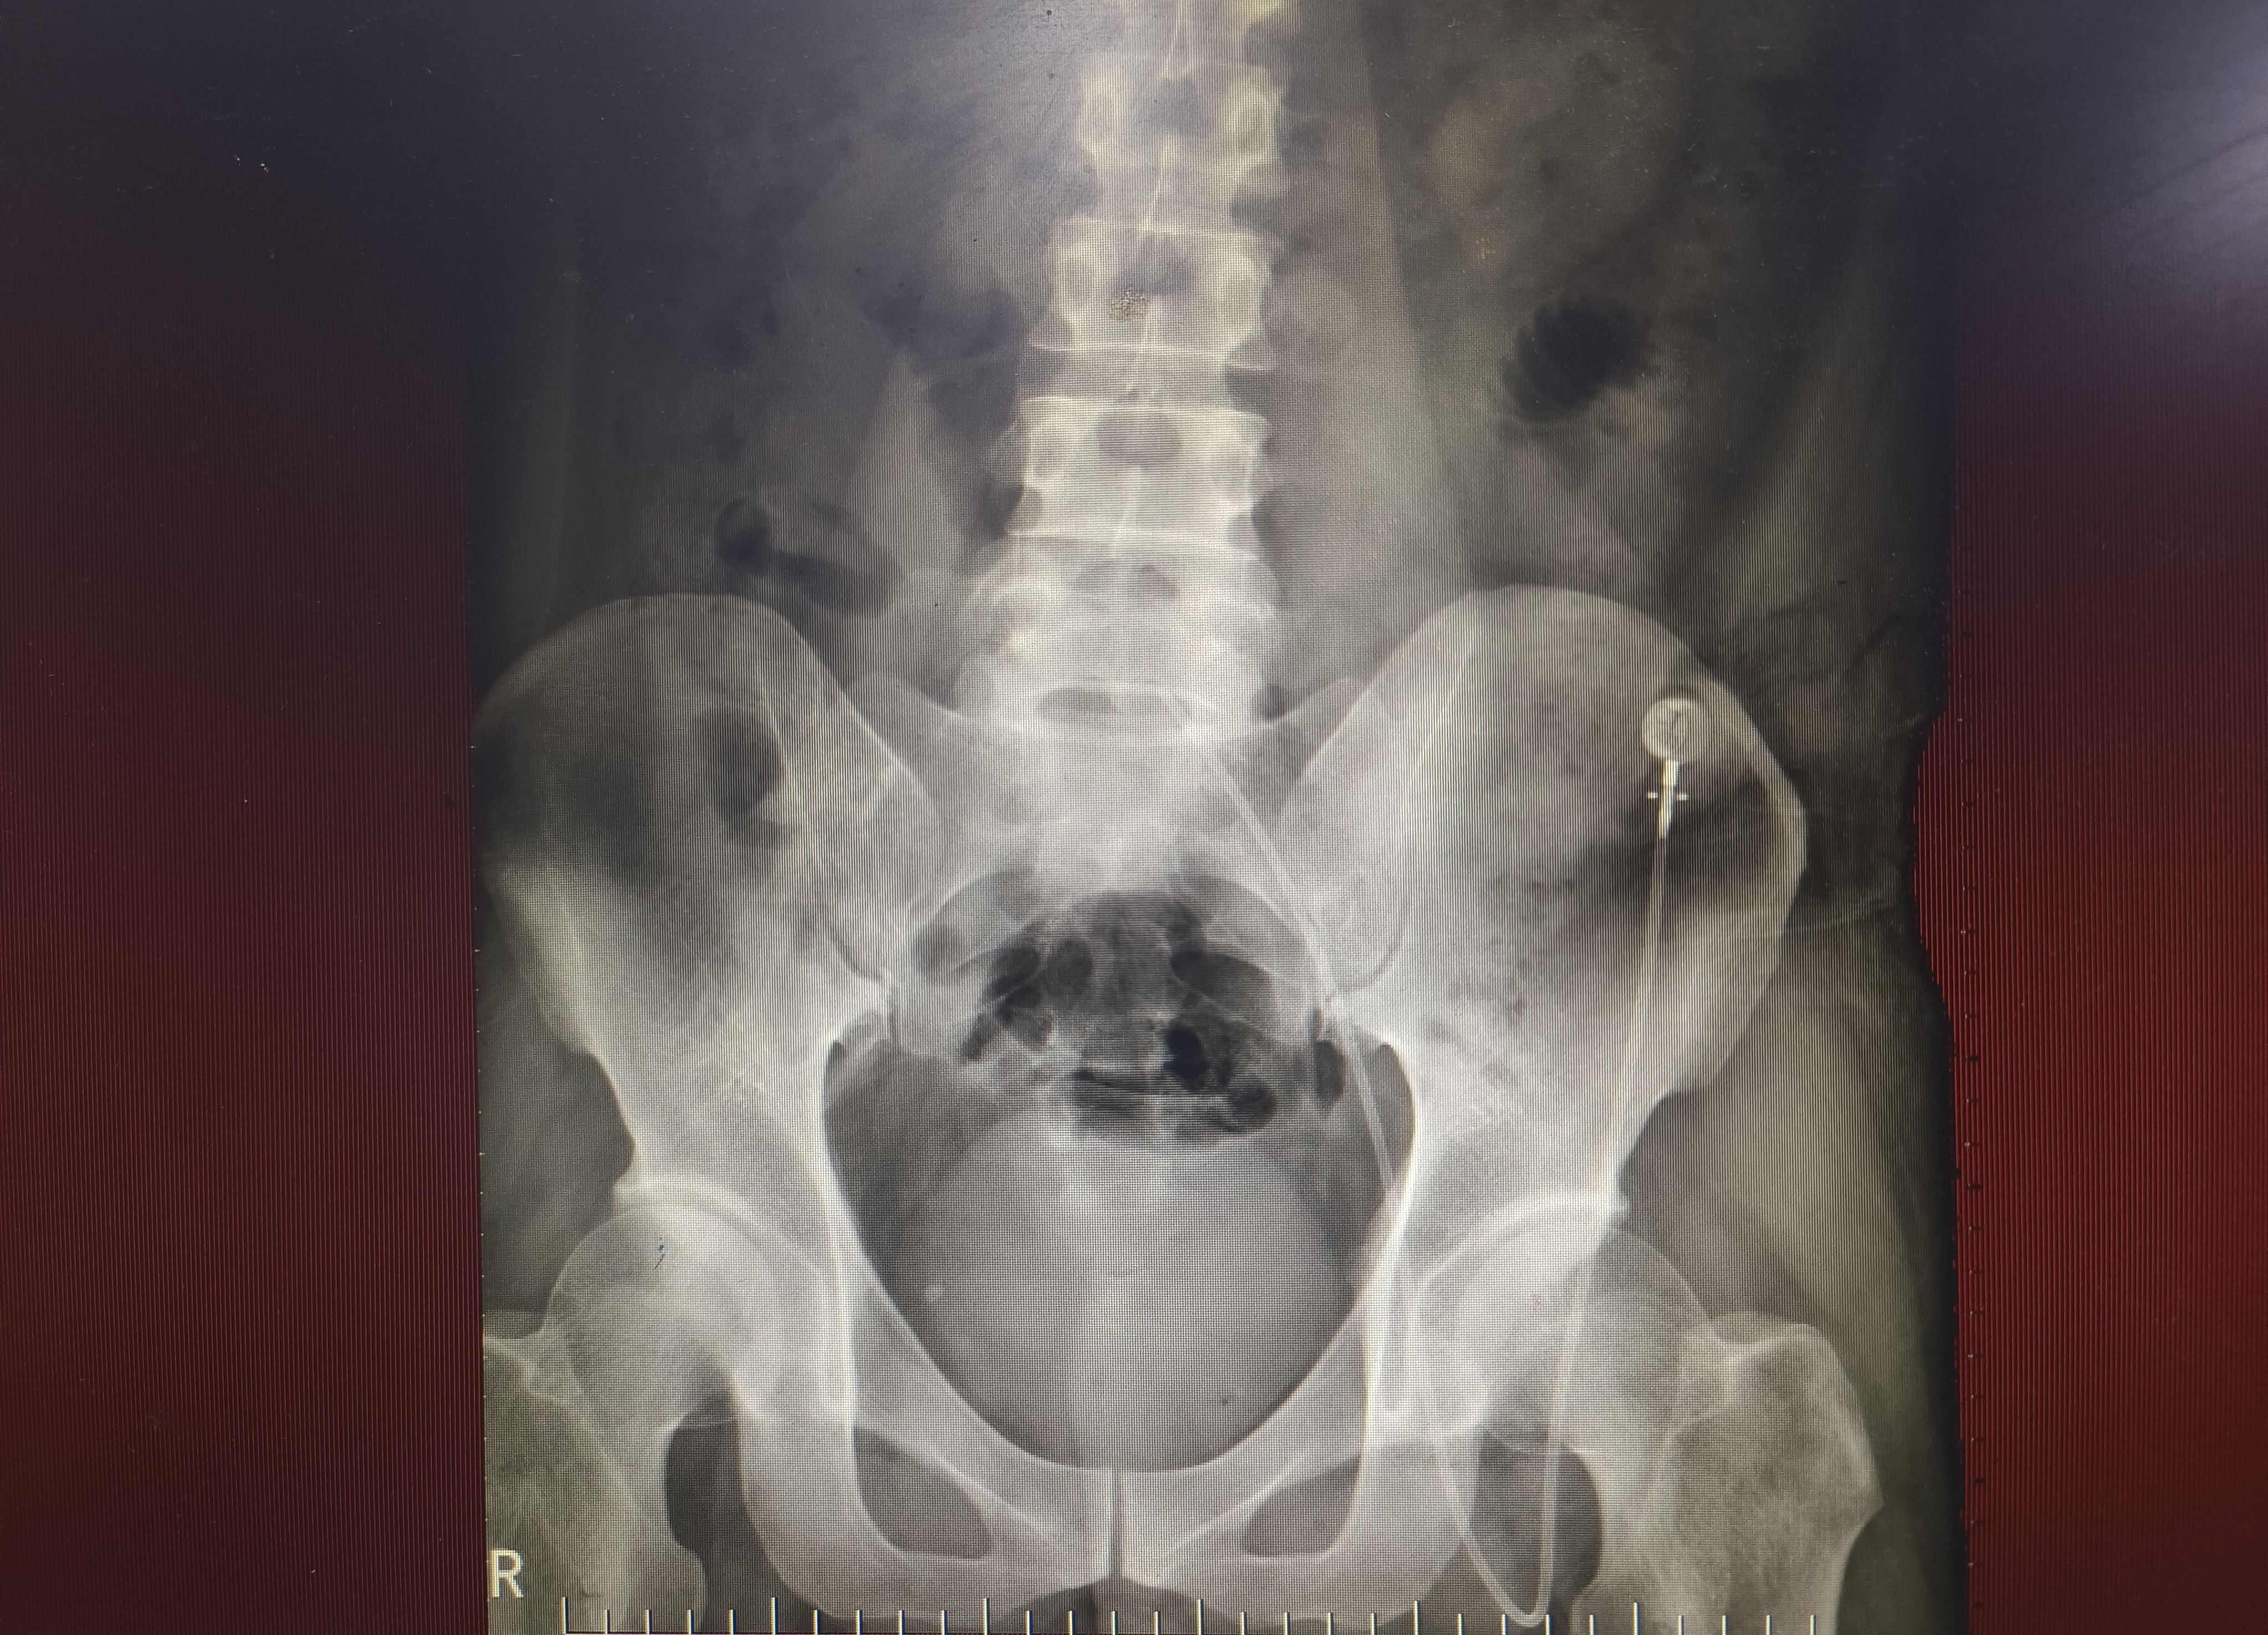

肝癌患者,上腔静脉阻塞合并颈部和上肢血管多处血栓,急需解决化疗输液难题,右侧曾有腹股沟斜疝,尝试左侧腹股沟入路,输液港底座置于左下腹壁,手术顺利,希望接下来的治疗能帮你跑赢时间✊🏻✊🏻